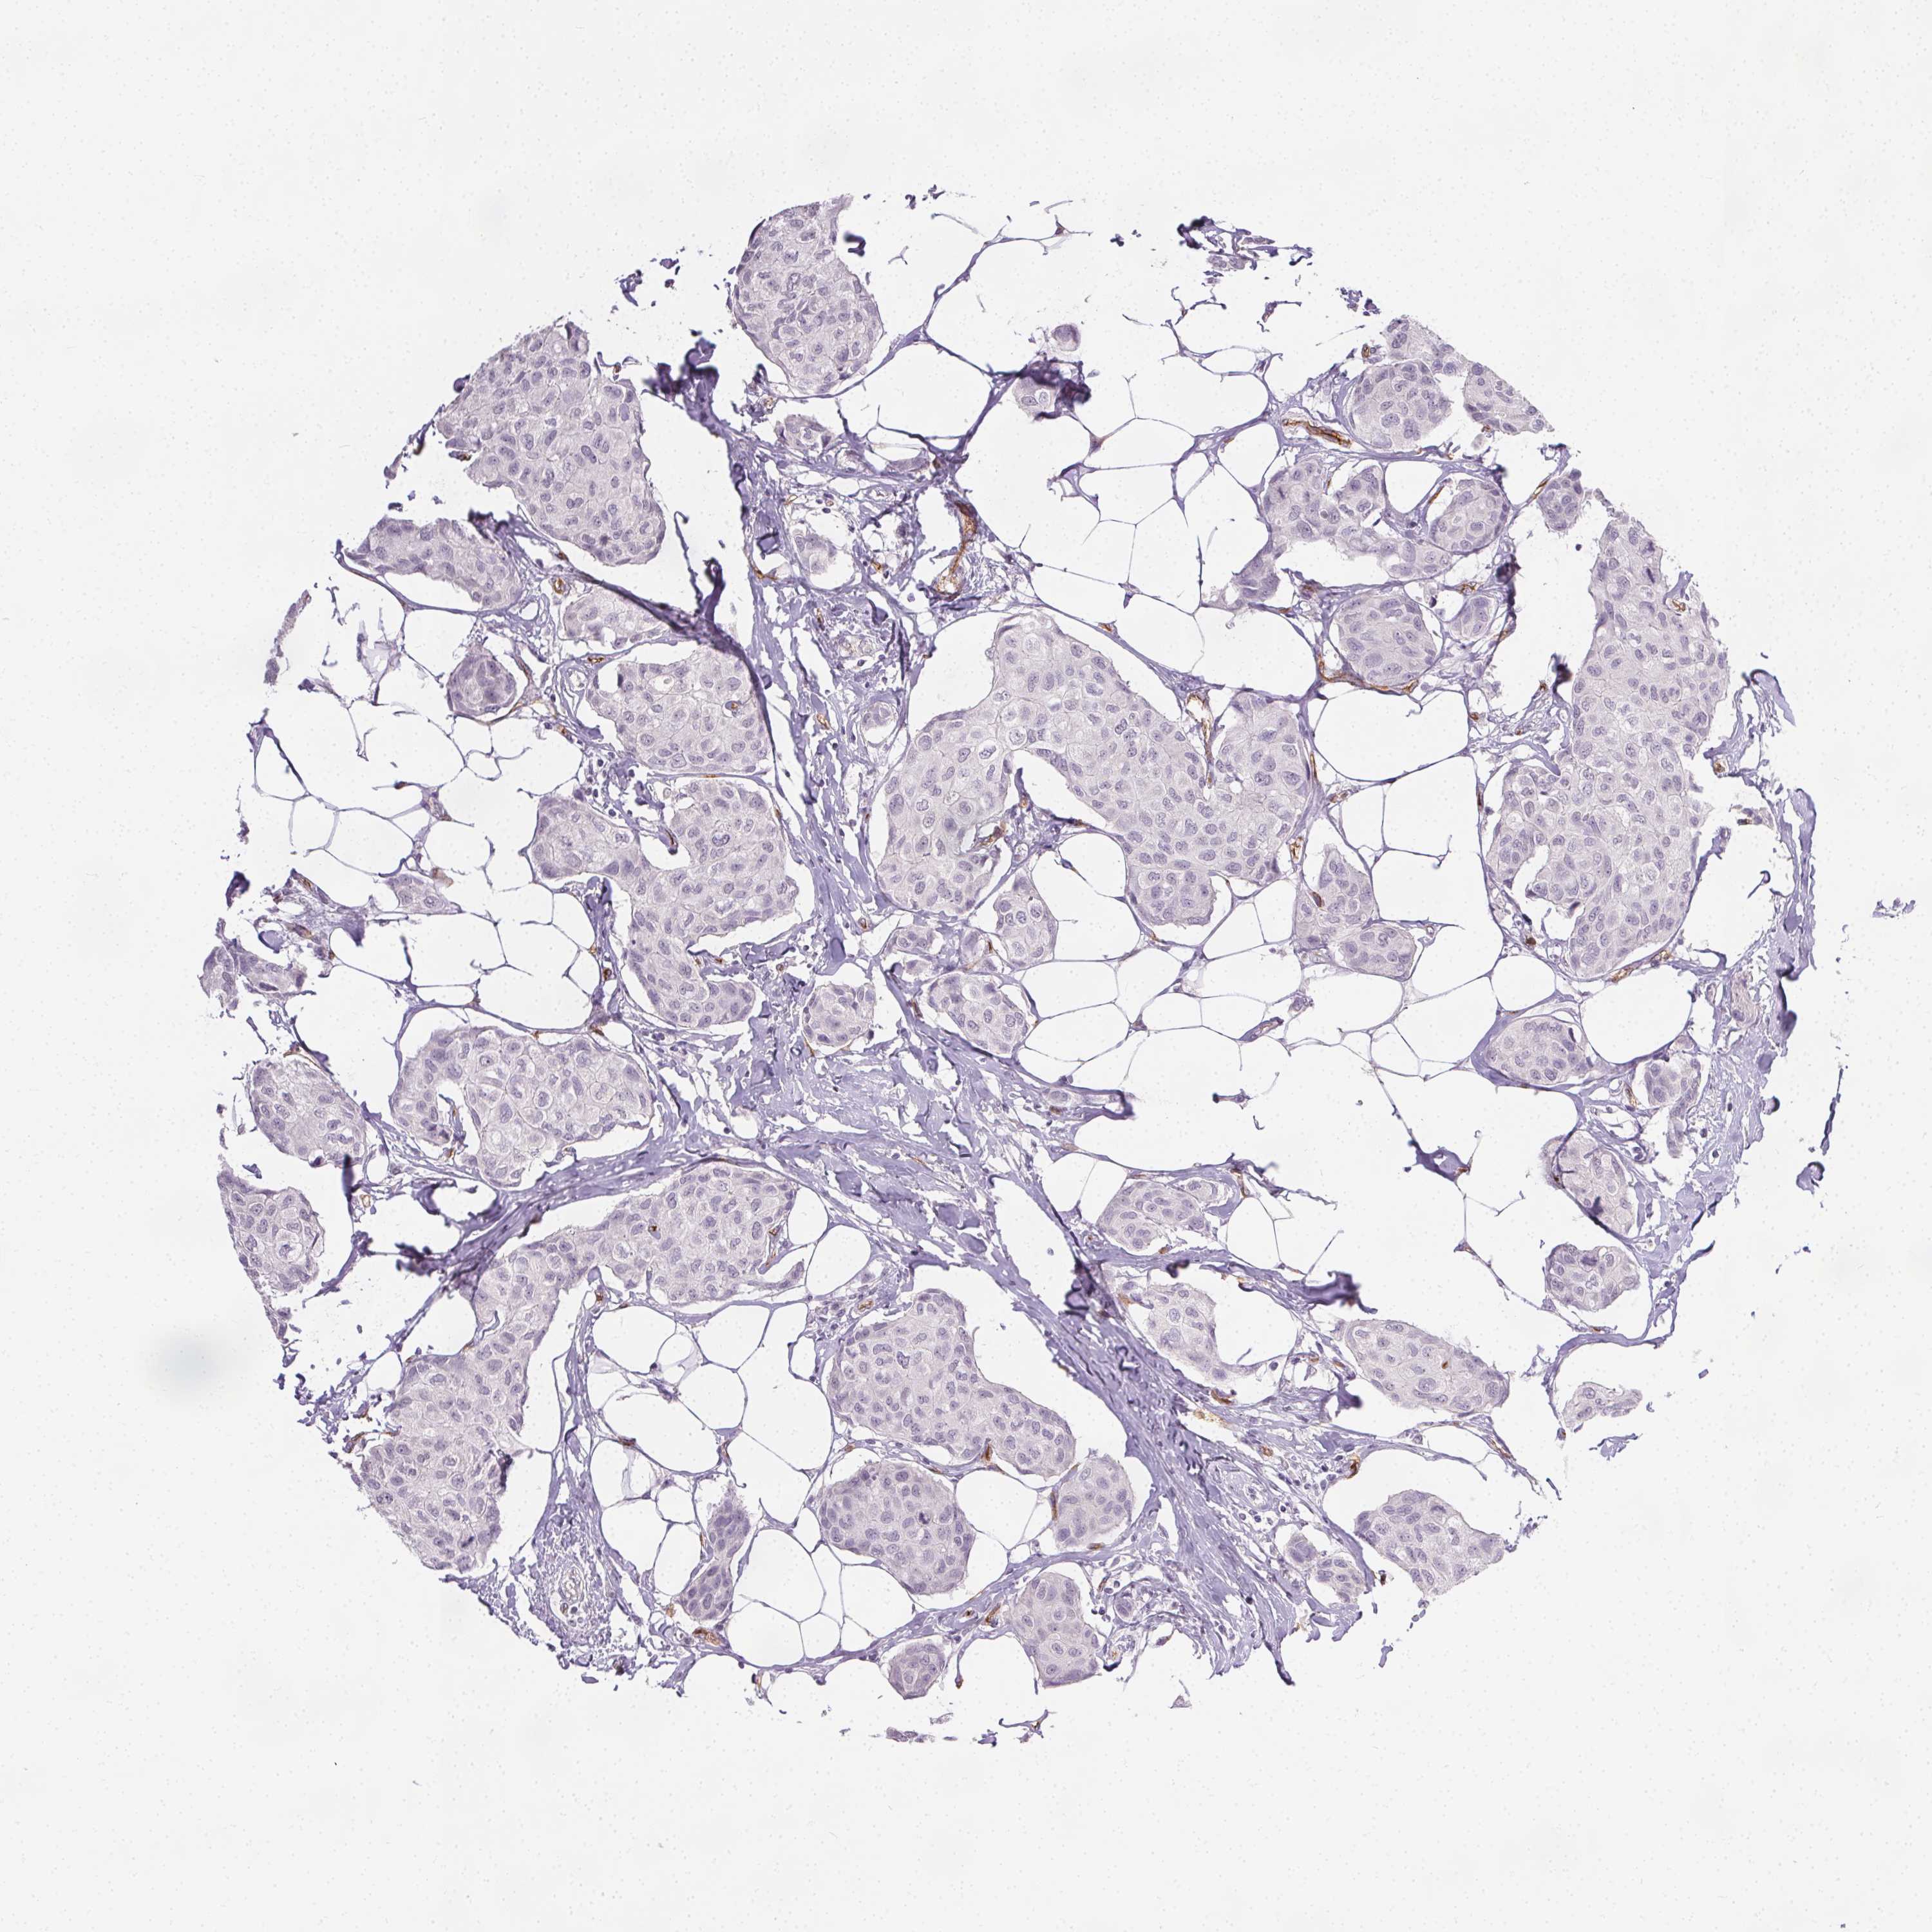

BRCA TCGA BRCA VALIDATION PROTEIN EXPRESSION